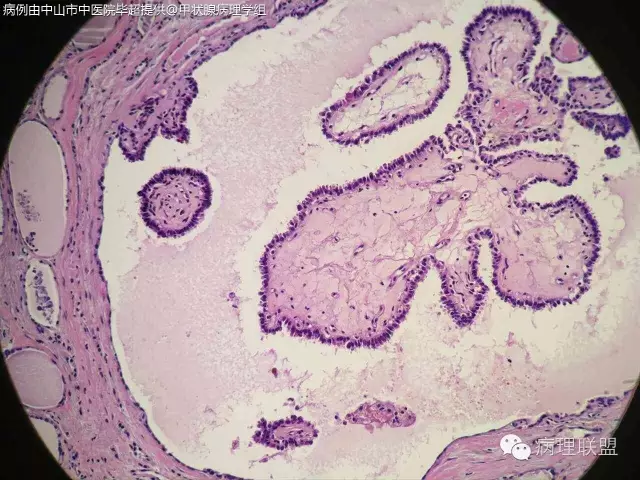

请教老师们一个病例,女,61岁,双侧甲状腺占位。(病例由西藏自治区人民医院 罗含欢 提供,致谢!)

没有看到浸润性生长,仔细看细胞核是否有乳头状癌的特征(核沟、毛玻璃样、加包涵体),图片不是很清楚,目前看上去应该是良性的,没有间质反应和砂粒体。浅见。

核不清,宽厚纤维间质,核重叠,应为乳头状癌

@罗含欢 结节性甲状腺肿伴出血囊性变,部分滤泡上皮乳头状增生

结甲,部分腺上皮乳头状增生

@毕超 上一例跟你这个不一样。诊断结节性甲状腺肿伴滤泡上皮乳头状增生就可以了。唯一有点怀疑的是那小小灶真的乳头状结构的区域,虽然不是很清楚,但是可以隐约看出其细胞排列相当的整齐,规则。跟你这例完全不一样,核也是位于同一水平,个人看法,不对的地方请老师们指正

第一例乳头内有滤泡,第二例是真正纤维轴心,两例乳头不一样